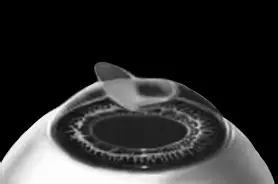

Рис. 8.Роговичный лоскут укладывается на место.

Иллюстрация с сайта Международного лазерного центра www.optics.ru

Края роговичного лоскута осушают сухим тупфером. Влага, оставшаяся под лоскутом в ямке роговичного ложа, высасывается в тупфер. Лоскут притягивает к ложу, как вакуумную присоску. Вакуумом начали, вакуумом закончили.